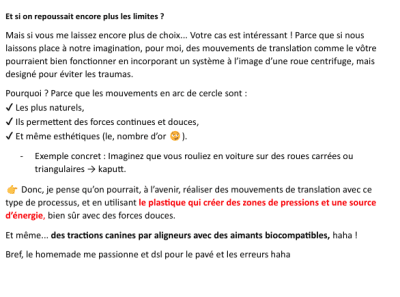

Etape 2 (photo figure 2) : Une fois la mésialisation de la canine faites le plus dure, je fais la mésialisation de mon bloc lat classique ou j’ai justement du recul

Solution Bonus – ATP-V modifié

Une base squelettique en 0.36, à vérifier pour s’assurer qu’elle est suffisamment rigide.

La face palatine des dents du secteur 1 est collée. Il s’agit de bases reliées à un anneau sur la barre palatine, avec des chaînettes permettant de tracter les dents une à une.

Un prolongement est ajouté à l’arrière des incisives maxillaires, ainsi qu’un autre partant de la face distale de la 11 jusqu’au niveau vestibulaire. Ce dispositif vise à limiter les mouvements parasites. Étant donné que les dents 13/14/15 et 16 ne seront pas directement prises en charge dans l’Ac, mais uniquement tractées par l’ATP-V, ces mouvements parasites resteront présents, bien que réduits à un taux tres faibles par rapport à tous les systèmes grâce notre traction direct sur l’ATP-V et sans prise en charge dans l’Ac des dents tractées.

Certes, cet appareil sur mesure représente un coût légèrement supérieur, mais il permet un gain de temps au fauteuil en ne nécessitant que le changement des chaînettes. De plus, il assure une efficacité accrue, permettant ainsi de se concentrer sur d’autres aspects du traitement.